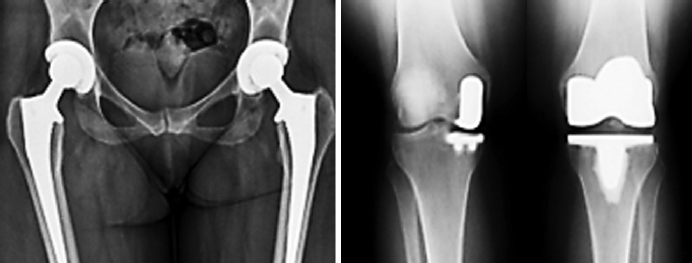

4) хирургическое лечение, в основном представленное тотальным эндопротезированием, а также использование классических опиоидов как единственной альтернативы для пациентов, которым противопоказано хирургическое вмешательство (эндопротезирование и др.). В настоящее время каждому восьмому пациенту с ОА через 13 лет с момента выявления болезни требуется хирургическое лечение – эндопротезирование (рис. 21–23).

Рис. 21. Протезирование коленного сустава при остеоартроза / Fig. 21. Knee replacement for osteoarthritis

Рис. 23. Протезирование тазобедренного сустава при остеоартрозе (вверху). Ренгенограммы тазобедренных и коленных суставов после протезирования (внизу) / Fig. 23. Hip replacement for osteoarthritis (above). X-rays of the hip and knee joints after prosthetics (below)